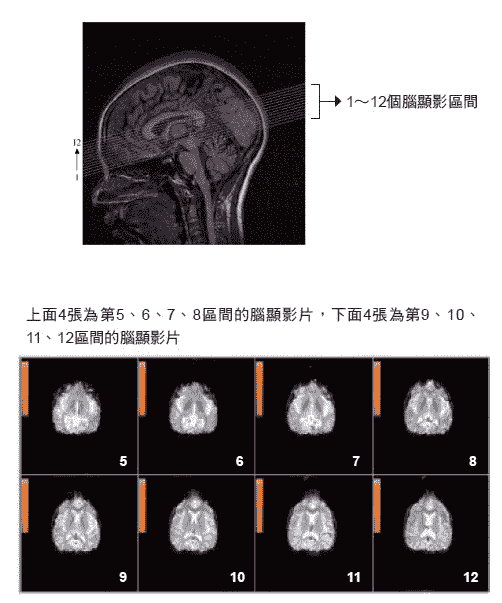

一九九八年,我们也用功能性磁造影(functional magnetic imaging,简称fMRI)技术测量了高桥小姐手指识字时大脑各部位的活动情形(如一○四页图2-15所示),并将大脑切割成十二条细长紫色线分隔的区间,包括视丘、松果体、胼胝体等部位。

图2-15 手指识字时,用fMRI测量大脑各部位活动情形

|  |

|

| 红色部位是开天眼前后信号变化较大的部位。从第7张脑显影片可看到,左脑听觉部位有变化,第8张起,脑中央部位一些区域有很大的变化。 |

高桥一手操控按钮,开天眼时按一下作为信号,帮助分析数据。

如右图2-15下方显影图所示,上排是第五、六、七、八的四片区域;下排是第九、十、十一、十二的四片区域,以及开天眼前后信号变化图,红色部位是较大的变化。很明显的是,从第七张左脑听觉部位有变化,第八张起中央部位一些区域有很大的变化。